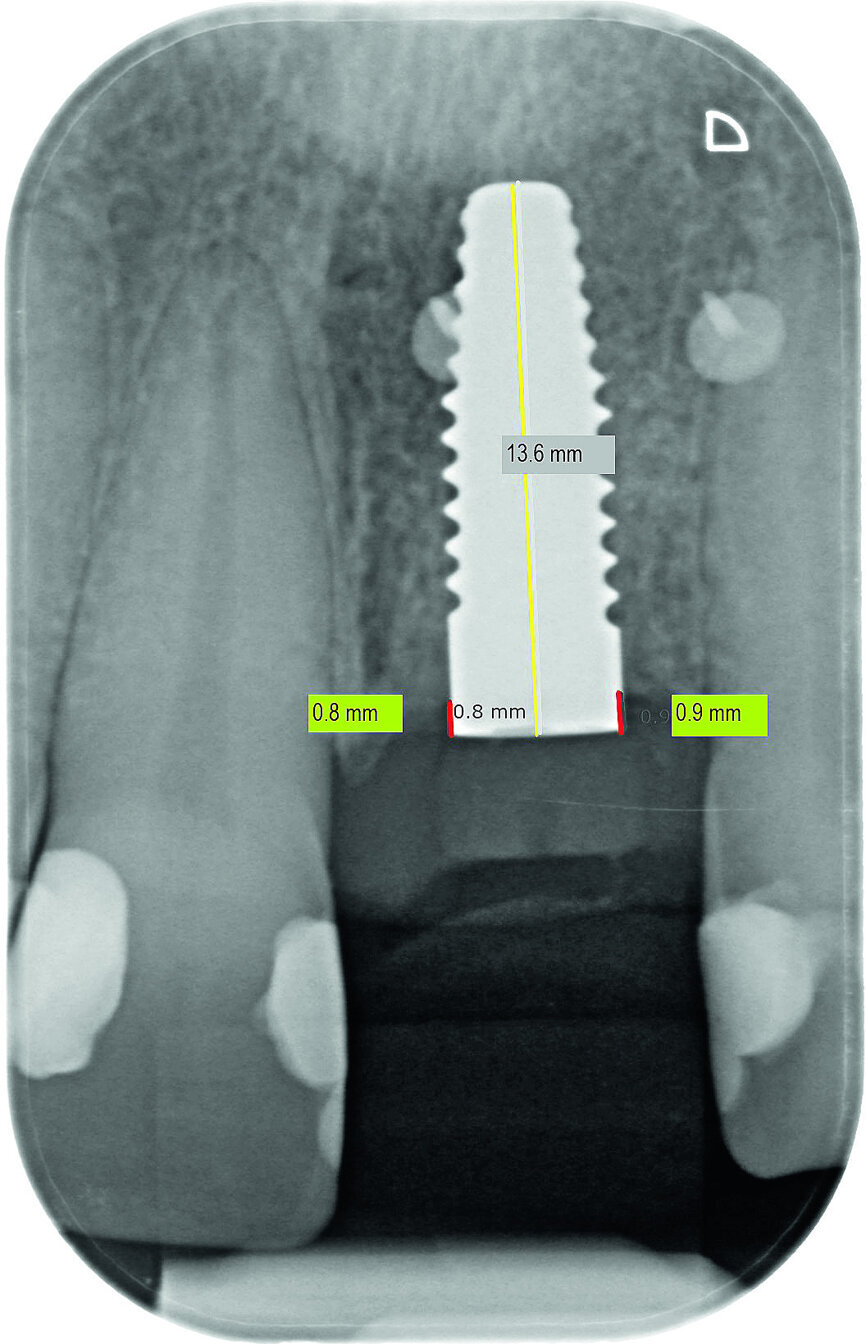

Fig. 13a: Bone resorption was detected after six months and bone gain after 12 months. The yellow line represents the actual implant length (13.6mm). The red lines indicate the mesial and distal distances from the top of the implant to the first bone contact.

Fig. 13b: Bone resorption was detected after six months and bone gain after 12 months. The yellow line represents the actual implant length (13.6mm). The red lines indicate the mesial and distal distances from the top of the implant to the first bone contact.

Bone resorption was detected six months after exposure (mesial bone: 0.6 mm; distal bone: 0.4 mm), and a gain of bone was observed 12 months after exposure (mesial bone: 0.0 mm; distal bone: 0.3 mm; Figs. 13a–c). In accordance with the findings in the relevant literature, bone resorption in our patient was the greatest in the first six months.16 However, the literature findings are in reference to one-piece ceramic implants, in contrast to the two-piece implant system used in this case. This phenomenon of bone resorption is a relatively rare occurrence in implantology and should be confirmed by evidence-based long-term studies before a definitive conclusion can be drawn. Evaluations are in progress.